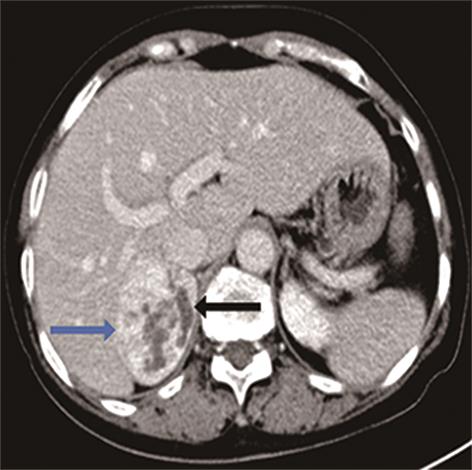

• 嗜铬细胞瘤及副神经节瘤不同生化表型的CT征象对比研究

2024, 49(2):203-209. DOI: 10.13406/j.cnki.cyxb.003433

摘要 (51) HTML (33) PDF 3.10 M (96) 评论 (0) 收藏

摘要:目的 分析生化阴性嗜铬细胞瘤及副神经节瘤(pheochromocytomas and paragangliomas,PPGLs)的电子计算机断层扫描(computed tomography,CT)征象是否有别于生化阳性PPGLs,同时了解生化阳性PPGLs不同表型的CT征象是否存在差异。方法 回顾性分析131例PPGLs患者的术前腹部增强CT图像,包括肿瘤位置、大小、形态、囊变坏死、液-液分层、钙化、向心结节状强化、肿瘤内粗大血管、强化包膜、绝对廓清率及相对廓清率。根据生化水平,将患者分为生化阳性组和阴性组,阳性组进一步分为去甲肾上腺素型、肾上腺素型及多巴胺型。比较各组及各表型间的CT征象差异。结果 相较于生化阴性组,阳性组PPGLs更大(Z=-2.064,P=0.039)、囊变坏死(χ2=6.610,P=0.010)及向心结节状强化(χ2=3.909,P=0.048)的比例更高;相较于去甲肾上腺素型,肾上腺素型PPGLs更大(Z=-2.036,P=0.042)、强化包膜比例更高(χ2=7.242,P=0.007)。结论 肿瘤大小、囊变坏死及向心结节状强化的CT征象有助于术前诊断生化阴性PPGLs,肿瘤大小及强化包膜有助于解释去甲肾上腺素型及肾上腺素型PPGLs不同临床表现产生的机制。